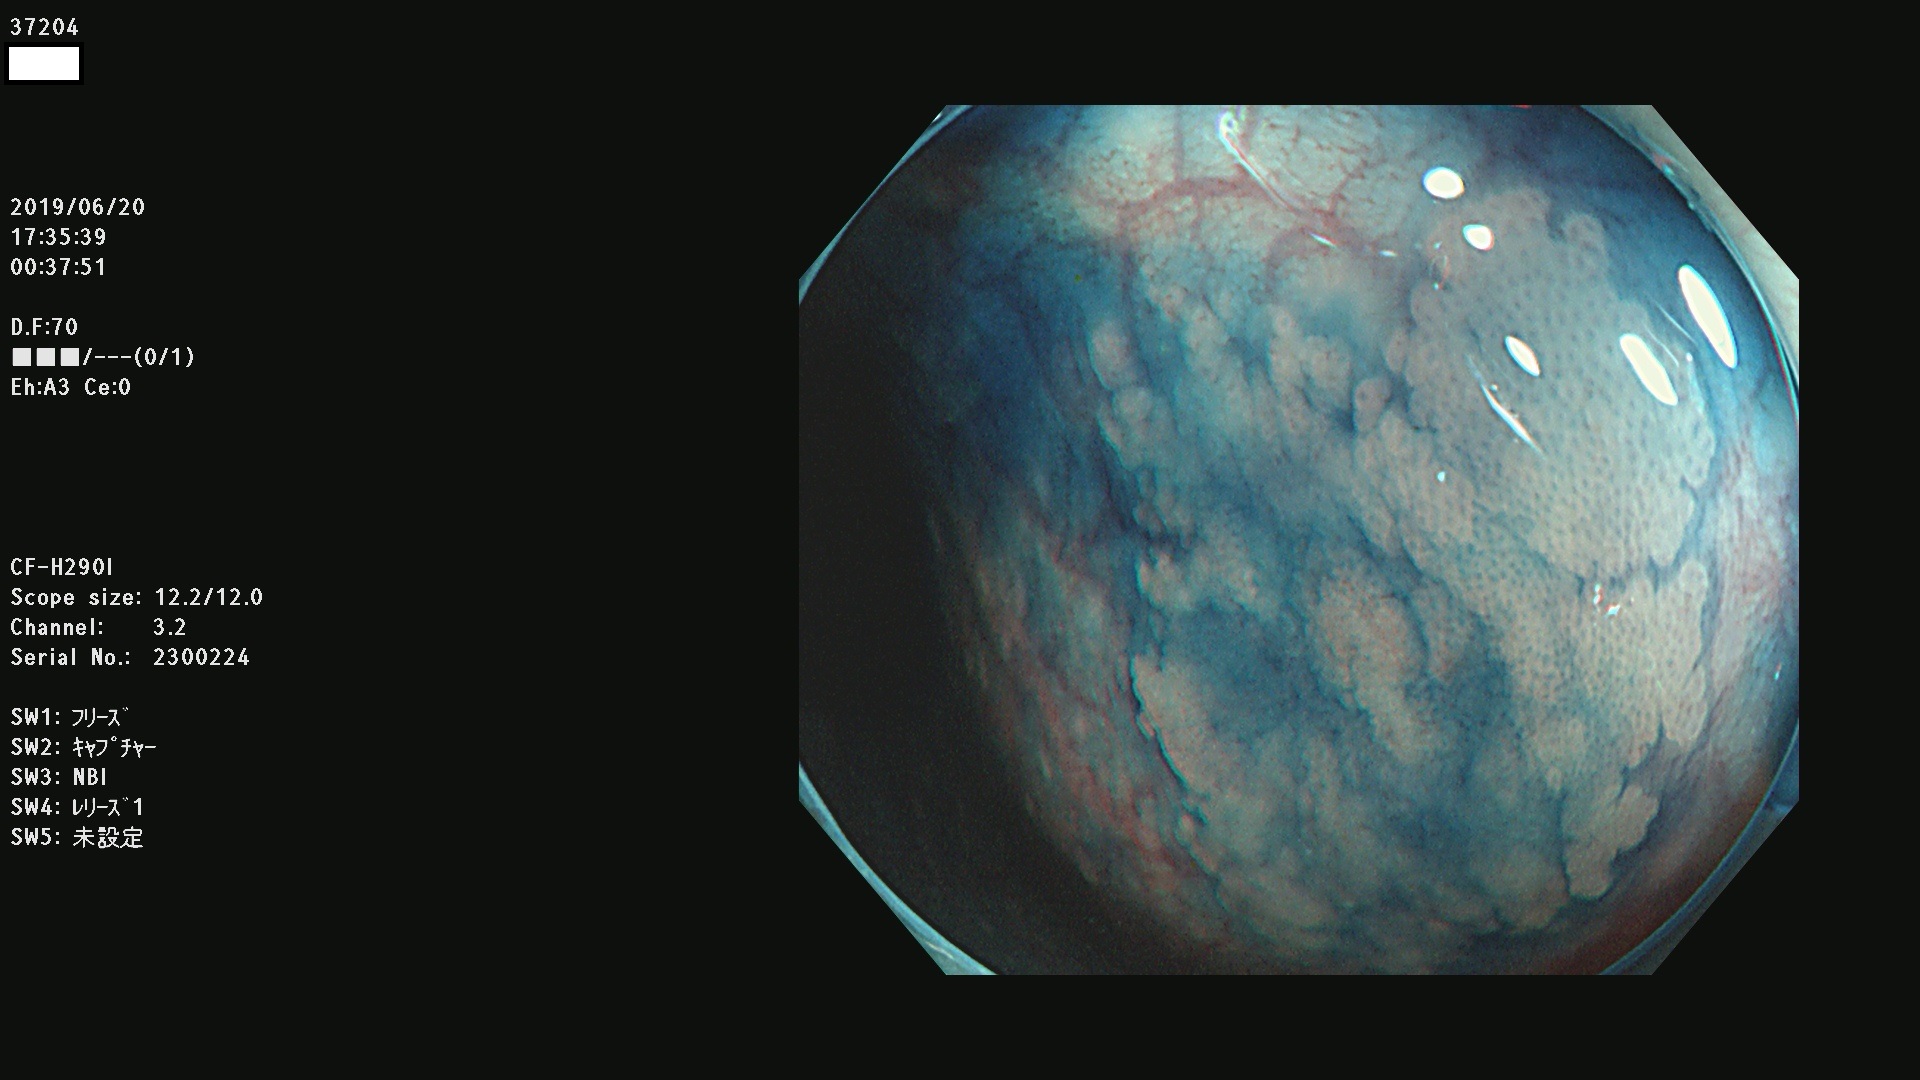

37200 37203 37204 37207 37208 37209 37210 37211 37212 37213 37214 37215 37216 37217 37220 37221 37222 37224 37225 37228 37229 37230 37232 37233 37234 37235 37236 37238 37241 37242 37243 37244 37245(SSAPのみ) 37247 37249 37250 37251 37252(SSAPのみ) 37254 37256 37257 37258 37259 37260(SSAPのみ) 37261(SSAPのみ) 37262 37263 37264 37265 37266 37267 37268(SSAPのみ) 37269 37271 37273 37274 37276 37277 37278 37279 37280 37281 37282 37284(SSAPのみ) 37285 37286 37288 37289 37290 37292 37293 37295 37296 37297(SSAPのみ)

発見困難で危険性の高い平坦型病変(上記100名より抽出)